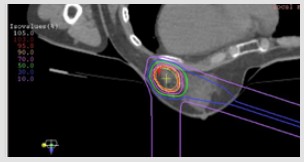

図 照射範囲と線量分布の例